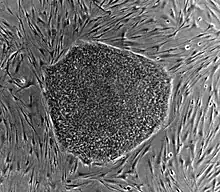

A : cellules souches humaines encore indifférenciées.

B : cellules nerveuses.

Les cellules souches adultes sont beaucoup plus rares, puisqu'une fois le développement terminé, la nécessité de proliférer peut devenir dangereuse. Les cellules souches perdurent donc en des endroits restreints dans chaque tissu ; ces niches ont des mécanismes de maintien complexes et sont régulées pour ne produire que les cellules nécessaires au maintien d'un organisme fonctionnel.